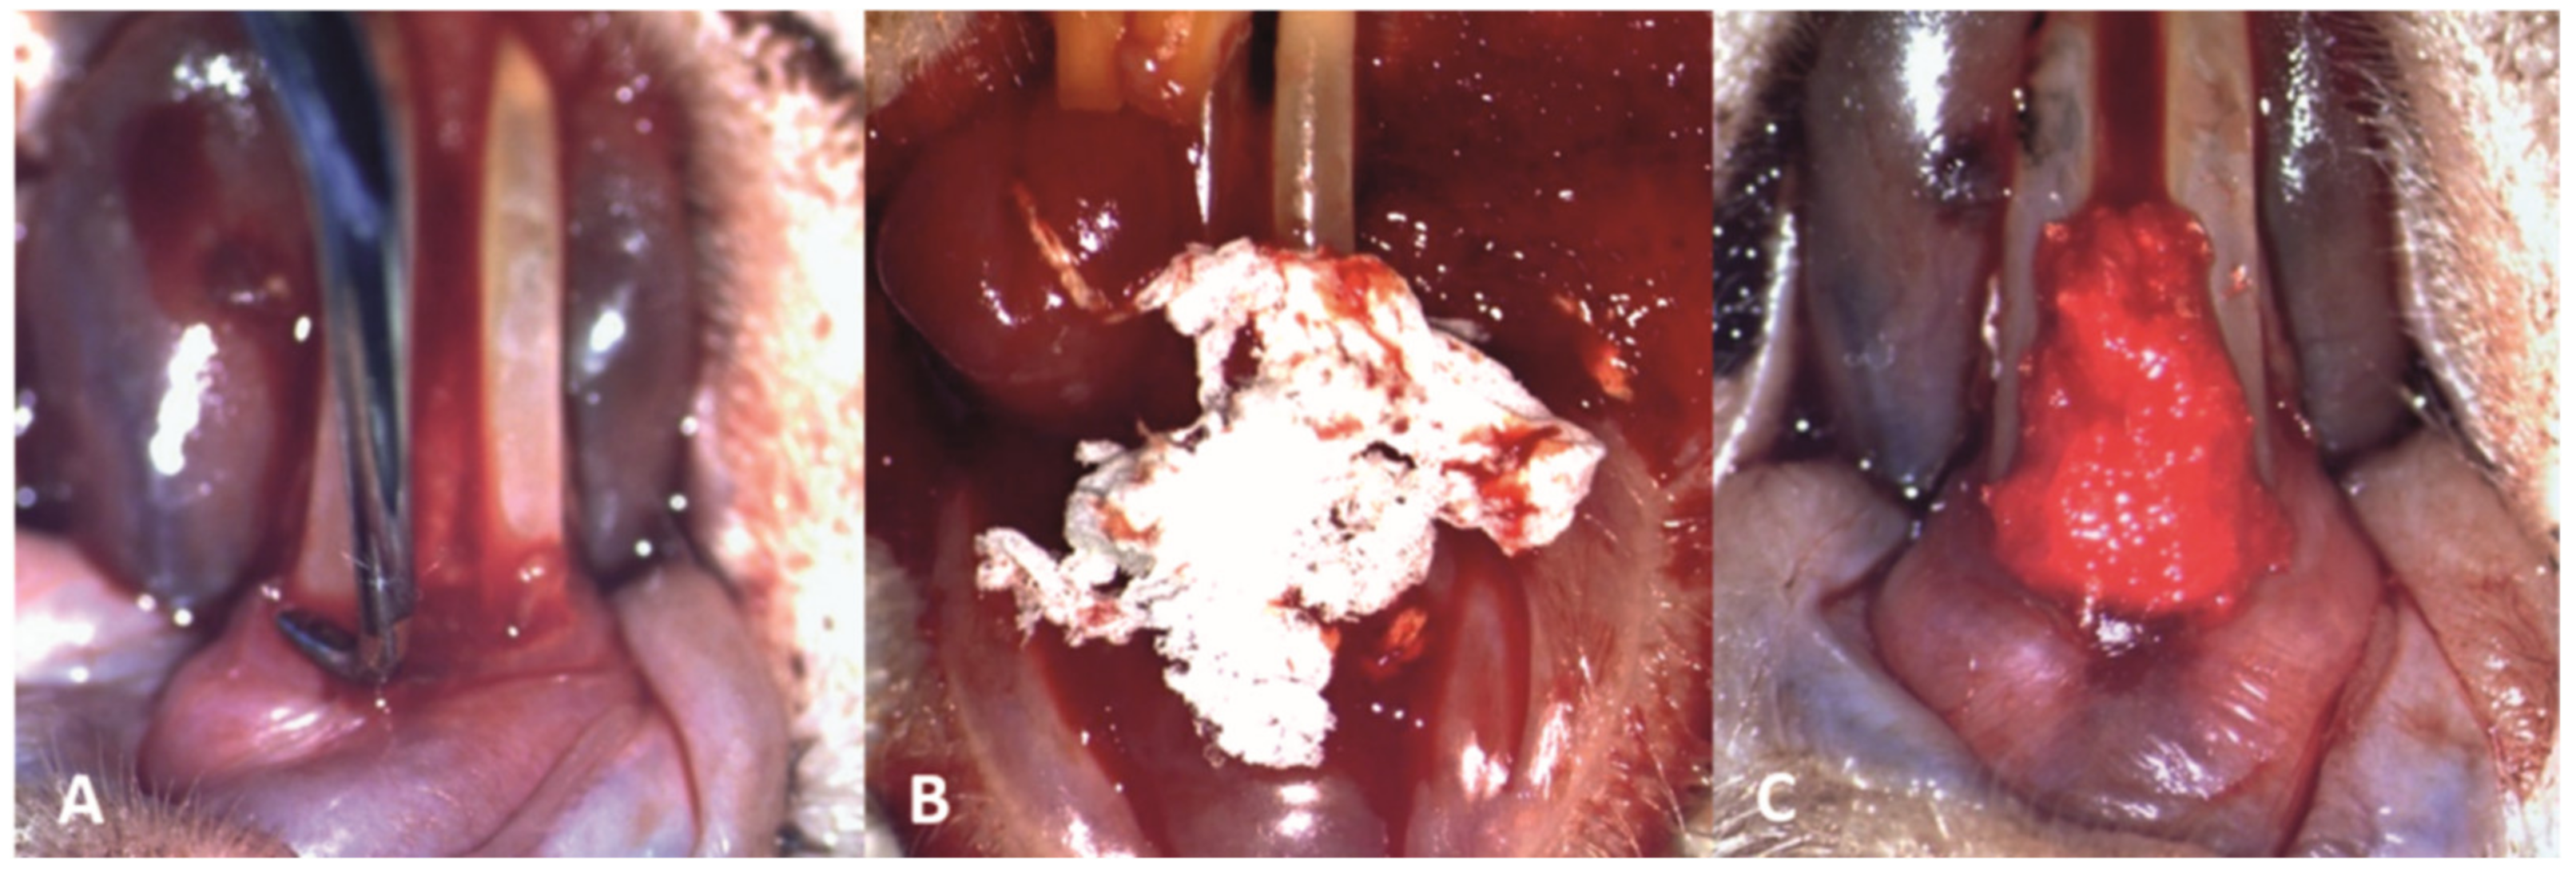

The periodontal pocket loaded with the new biomaterial was covered with a mucoadhesive buccal film, which became malleable and adhered to the periodontal tissues after hydration with sterile saline solution and the subsequent contact with saliva (Figure 5).

Figure 5. Clinical aspect after the application of the mucoadhesive buccal film covering the periodontal pocket loaded with the electrospun nanofibers.